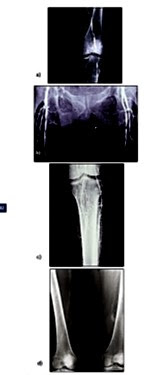

Figura 13. Patrones angiográficos característicos de la ateromatosis en

la DM: Estenosis politopicas en el sector femoro poplíteo a); afectación de la

arteria femoral profunda b); Obliteracion d ellos troncos tibio peroneos c); La

calcificación arterial, descrita por Monckeberg, es un hallazgo frecuente d).